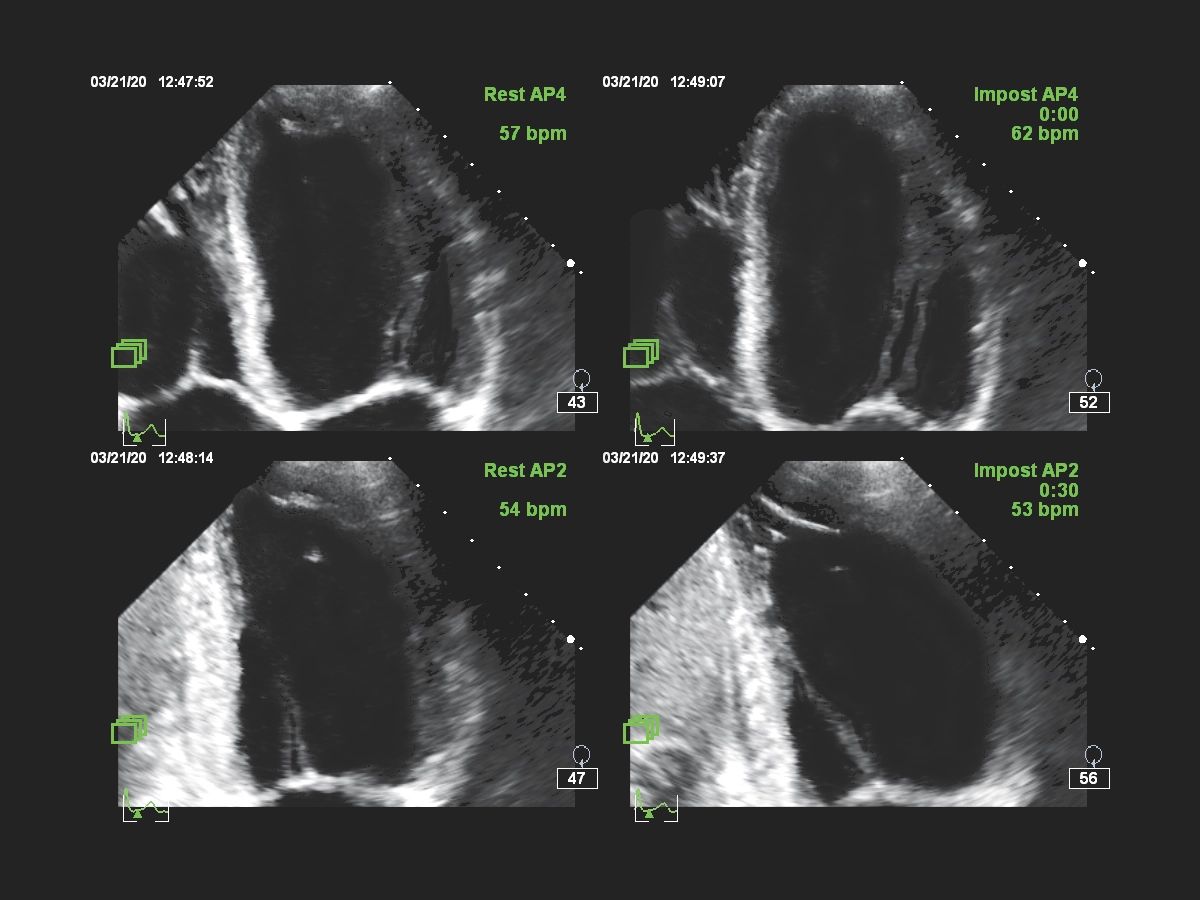

Функции для кардио-исследований

- Stress Protokol - стресс эхокардиография

- GI 3DQ - количественный анализ 3D

- TDI - тканевый допплер

- Strain Q - функция для оценки скорости движения стенок миокарда

- A2DQ - автоматическое распознавание границ камер сердца и расчет площади, объема левого желудочка и параметров систолы и диастолы левого желудочка, расчет фракционной площади, фракции выброса, максимальной скорости выброса, максимальной скорости быстрого наполнения и фракции предсердного наполнения

- aCMQ - Анализ параметров общей и конкретной сократимости камер сердца

- CMQ Stress - стресс эхокардиография для оценки глобальной и регионарной сердечной функции в различных состояниях

- Режим Стресс-эхо